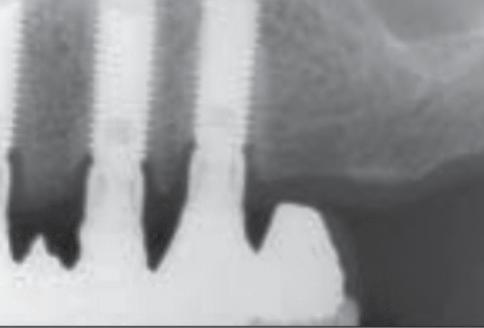

20A, 20B). A periapical radiograph demonstrated crestal bone present at the level of the implant platforms, suggesting successful regeneration and osseointegration (Fig. 21).

Figure 21: Periapical radiograph taken approximately 2 weeks after delivery of the final restorations. Excellent bone regeneration associated with the two implants, #7 in particular, is appreciated

a D-B root amputation. It served temporarily as a distal abutment for the partial prosthesis following restoration of the occlusal vertical dimension. The patient was advised of the necessity of implant therapy for a more stable rehabilitation of the maxillary right quadrant. Three 16-mm-long machined-surface Screw-Vent implants (CoreVent System, Encino, CA) were placed to replace the maxillary right premolars and first molar. In November 1991, the abutments were connected, and an implant-supported fixed partial prosthesis with a distal cantilever was placed. The patient was seen every 6 months for maintenance. Periapical radiographs were obtained annually of the patient’s right side (Figs 1 and 2).

The peri-implant bone level was found to be stable at the level of the first thread after 9 years of loading (Fig 3).

Prosthetic failure of the maxillary left premolars and first molar occurred in October 1999. The fixed partial prosthesis became loose due to recurrent decay and poor crown-to-root ratio. It was decided to extract the remaining teeth and convert to an implant-supported fixed restoration. Three Brånemark implants (Nobel Biocare, Göteborg, Sweden) were placed in the maxillary left quadrant, and the patient was referred to her dentist for the placement of a temporary removable prosthesis to restore esthetics and function while implant osseointegration was achieved. The dentist removed the maxillary right implant-supported partial prosthesis and placed an overdenture. The patient was seen in May 2000 for abutment connection on the maxillary left implants. Periapical radiographs were obtained to assess the osseointegration. Severe bone loss was observed on the implants in the maxillary right first premolar site and the maxillary right first molar site (Figs 4 to 6).

At 1 year, the healing was remarkable (Fig 8).

Eighteen months later, the bone defects were nearly completely healed. Two implants were then added in the anterior maxilla, and the patient was rehabilitated 4 months later with a full maxillary implant supported fixed restoration. Periapical radiographs obtained 4 years later (Fig 9) confirmed the stability of the situation.

Fig 9 - Four years after control of the traumatic occlusion and the placement of an implant-supported full maxillary fixed prosthesis. Note the stability of the bone level